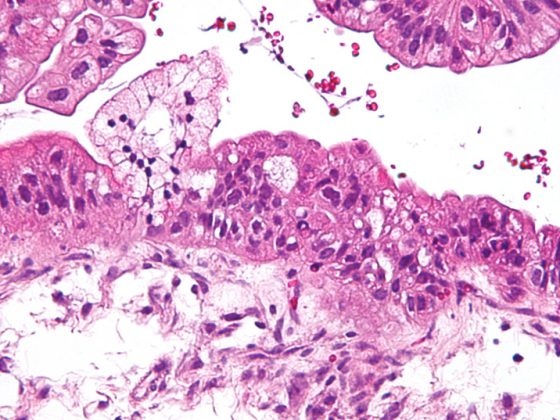

Die Strahlentherapie thorakaler Tumoren, insbesondere des Lungenkarzinoms, steht im Spannungsfeld zwischen der Zielstellung einer möglichst hohen Tumorkontrollwahrscheinlichkeit und der Vermeidung von Toxizitäten. Eine relevante Nebenwirkung stellt hierbei die radiogene Pneumonitis dar. Diese tritt mit einer zeitlichen Latenz von Wochen bis Monaten nach Abschluss der Behandlung auf.